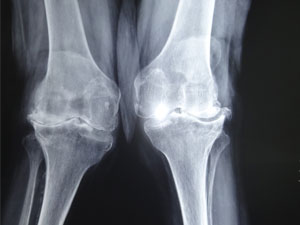

Valgus Deformity

Before Surgery